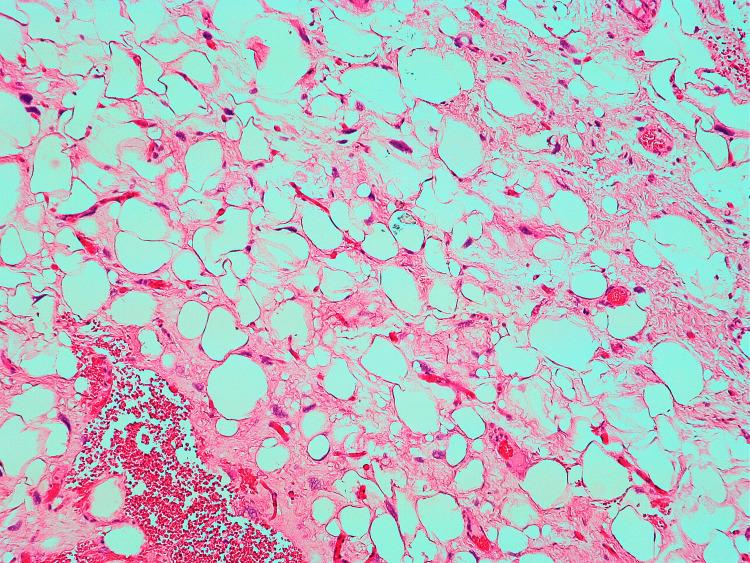

Giant paratesticular liposarcoma (PLS) is an uncommon tumour, often misdiagnosed pre-operatively, which presents as a painless scrotal mass. Early detection and prompt surgical management provide the best outcome. We present an 87-year-old patient with gradually enlarging, painless left scrotal swelling. Ultrasound on initial presentation suggested a benign hernia, resulting in an 11-month treatment delay. Computed tomography (CT) thereafter showed paratesticular scrotal mass measuring 14 x 8 x 7cm. Radical inguinal orchidectomy with high ligation of the spermatic cord was performed. Histopathology and cytogenetics confirmed PLS with both de-differentiated and well-differentiated features involving the spermatic cord margin. The patient had rapid progression to fatal lung metastasis within three months of surgery. Our case highlights that any suspicious fat swelling should be investigated thoroughly and excised promptly if paratesticular liposarcoma is suspected, as delayed management gives poor outcomes.

摘要

巨大睾丸旁脂肪肉瘤(PLS)是一种罕见的肿瘤,术前常被误诊,表现为无痛性阴囊肿块。早期发现并及时进行手术治疗可取得最佳疗效。我们报告一例87岁患者,其左侧阴囊逐渐肿大且无痛。初诊时超声提示为良性疝,导致治疗延迟11个月。此后计算机断层扫描(CT)显示睾丸旁阴囊肿块大小为14×8×7cm。行根治性腹股沟睾丸切除术并高位结扎精索。组织病理学和细胞遗传学检查证实为PLS,具有去分化和高分化特征,累及精索切缘。患者术后三个月内迅速进展为致命性肺转移。我们的病例强调,如果怀疑为睾丸旁脂肪肉瘤,任何可疑的脂肪肿胀都应进行彻底检查并及时切除,因为延迟治疗效果不佳。